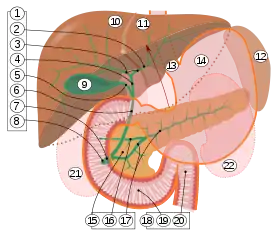

9. Gallbladder.

10–11. Right and left lobes of liver.

12. Spleen.

13. Esophagus.

14. Stomach.

15. Pancreas: 16. Accessory pancreatic duct, 17. Pancreatic duct.

18. Small intestine: 19. Duodenum, 20. Jejunum

21–22. Right and left kidneys.

The front border of the liver has been lifted up (brown arrow).[6]